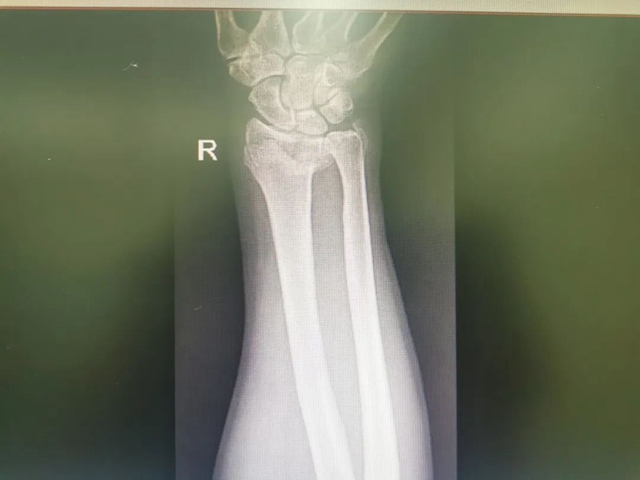

值守石棉县人民医院的骨伤科·正骨组王振龙副教授、手外·儿骨·烧伤整形组贺智榆主治医师接到伤员后,立即对其情况进行了检查评估,右侧腕关节掌侧、背侧肿胀明显,呈“餐叉样”畸形,影像结果提示:右侧桡骨远端粉碎性骨折、右侧尺骨茎突骨折。

王振龙、贺智榆讨论后,决定为其行桡骨远端粉碎性骨折切开复位内固定术。